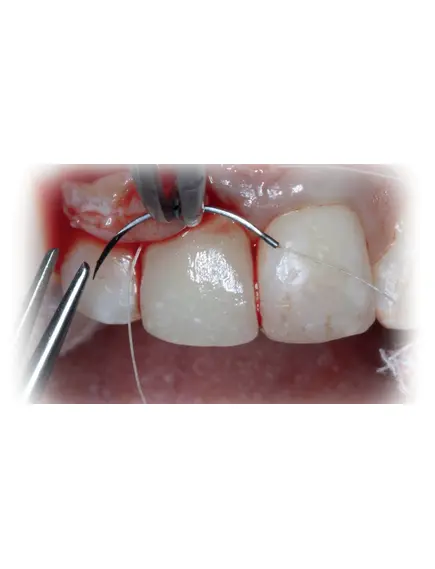

PERIODONTAL FLAPS & SUTURING TECHNIQUES & PRINCIPLES

Medical suturing is a crucial aspect of surgical medicine, used to close wounds after surgical procedures and repair tissue injuries to accelerate the healing process. The principles of medical suturing involve the use of specialized tools such as surgical needles and sutures.

- Suturing Techniques:

- Various suturing techniques are used in surgery, such as:

- Simple Interrupted Stitch

- Mattress Stitch

- Skin Stitch

- Fine Tissue Stitch